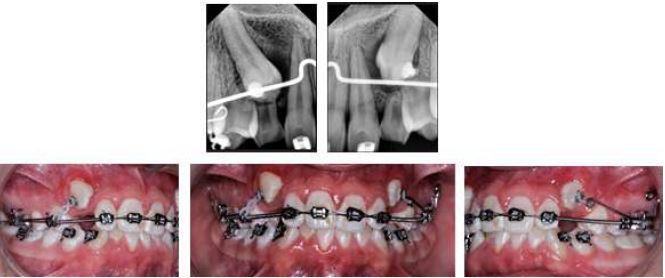

This is a 15-year-old female patient who attended a private clinic for orthodontic treatment. No alterations were described in the clinical records and systems review. Extraoral examination revealed a mesoprosopic-type face with a straight profile, adequate lip seal and facial symmetry. Intraoral examination revealed a Class II occlusal relationship, left subdivision, lower midline shifted 2 mm to the left, 40 % overbite, 3 mm overjet, presence of tooth 63 (FDI World Dental Federation -ISO- notation), moderate anterior-inferior crowding, and oval arches (Figure 2).

In the radiographic analysis, the orthopantomography (Figure 2) indicates, according to the Ericson and Kurol classification, that the crown of 23, mesodistal, was located in sector 4; In addition, the angle of the longitudinal axis of tooth 23 with the midline had a value of 50 °, which increased the risk of resorption of the lateral incisor (10) by 50 %, which is evident in the radiograph (Figure 2).

Initial Records Photography, Orthopantomography and Cone Beam Tomography, Case 1

FIGURE 2

The initial cone beam tomography shows 3D reconstruction, cuts in the different planes of tooth 23 and its relationship with 22 and 21, in which root resorption is evident. Source: the authors with permission from the patient.

Cone beam tomography analysis (Figure 2) showed moderate impaction of tooth 23 in the buccal position, whose coronal portion was close to the apical third of 21 and 22 with remodeling of the apical third of tooth 22. In Steiner's cephalometric analysis, anteroposterior and vertical assessment angles were adequate, resulting in a skeletal class I and neutral growth pattern.